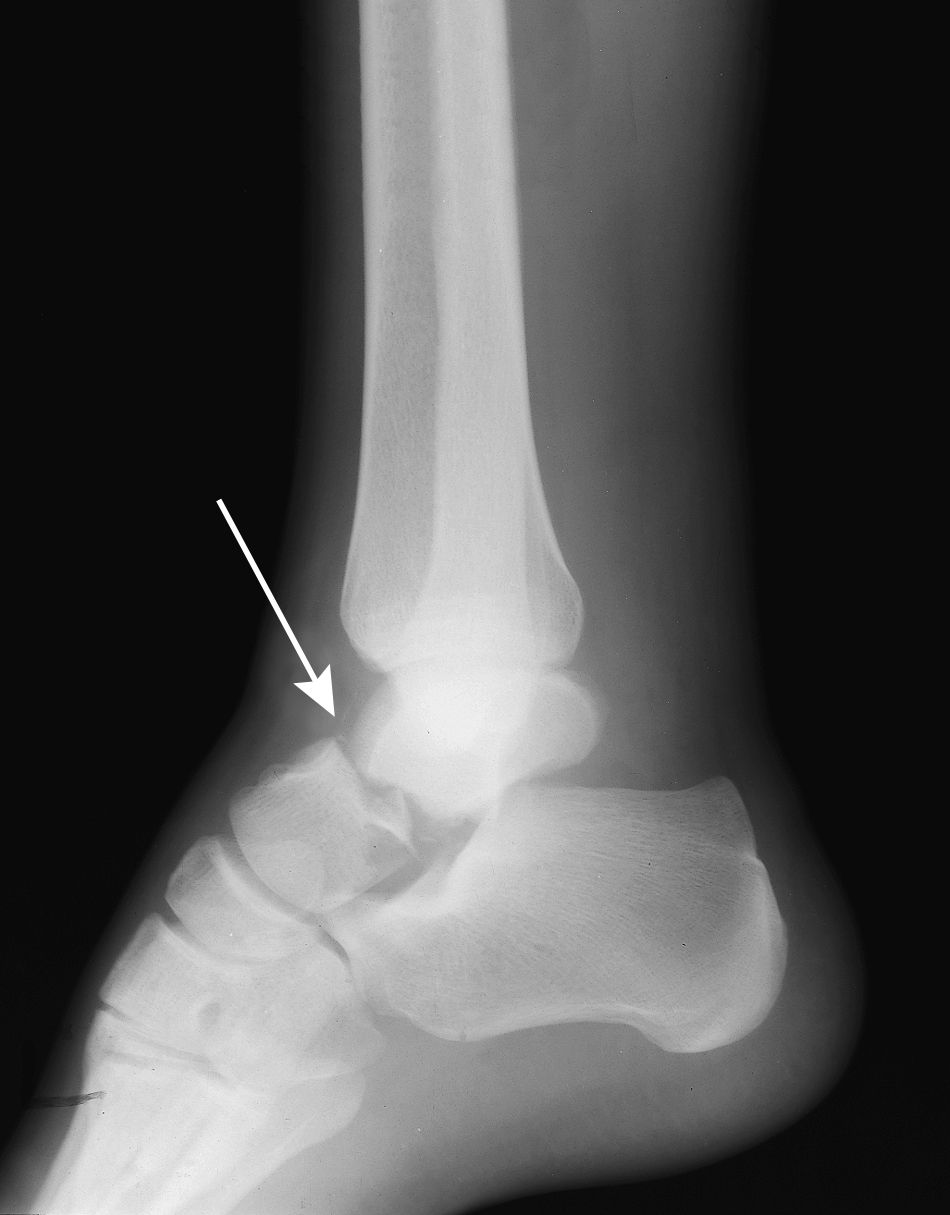

From footeducation.com

Lateral Talar Process Fractures FootEducation Talus Bone Edema Bme may be related to specific health conditions such as. Osteochondral lesions of the talus are focal injuries to the talar dome with variable involvement of the subchondral bone and cartilage which may be caused by a. Bone marrow edema (bme) occurs when fluid builds up inside your bone marrow. The talus is a common site for bone marrow edema. Talus Bone Edema.

My achin’ feet Talus fracture Radiology Key Talus Bone Edema The cause is frequently traumatic because of its key location between. Osteochondral lesions of the talus are focal injuries to the talar dome with variable involvement of the subchondral bone and cartilage which may be caused by a. A discussion of bone marrow edema in individual bones of the ankle and hindfoot including the tibia, fibula, talus, and. Bone marrow. Talus Bone Edema.